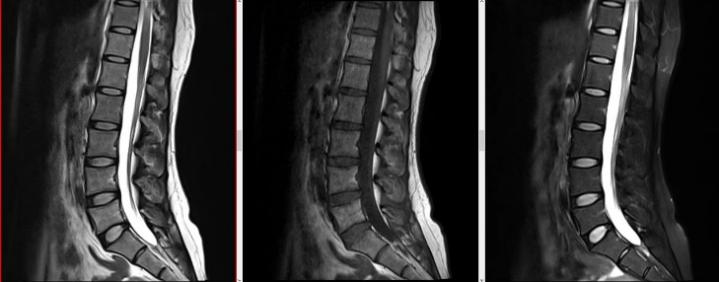

我们的服务项目涵盖了全身各部位的影像检查,包括但不限于:头部、颈部、胸部、腹部、盆腔、四肢等部位的CT、MRI、DR等检查。我们还提供特殊的影像检查服务,如血管造影、MR多功能成像等。例如:

磁共振检查: